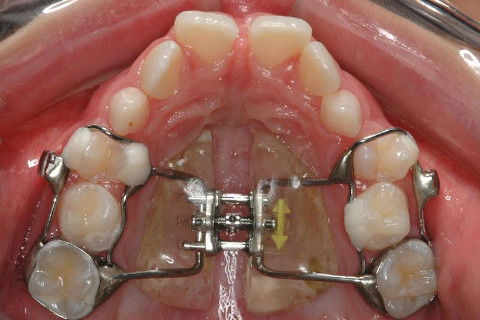

OCLUSAL SUP. INICIAL

HAAS MULTIFUNÇÃO.

HAAS MULTIFUNÇÃO ATIVADO.